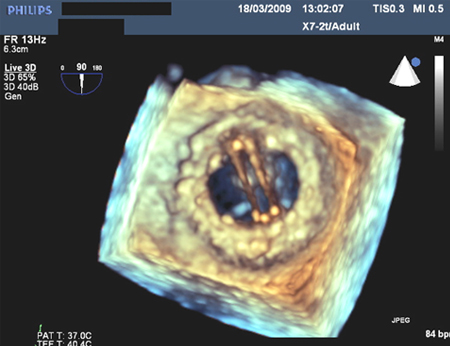

Valva mitral protética com regurgitação mitral intermitente

Do acervo de Prakash P. Punjabi

Veja esta imagem em contexto nas seguintes seções:

Vídeos